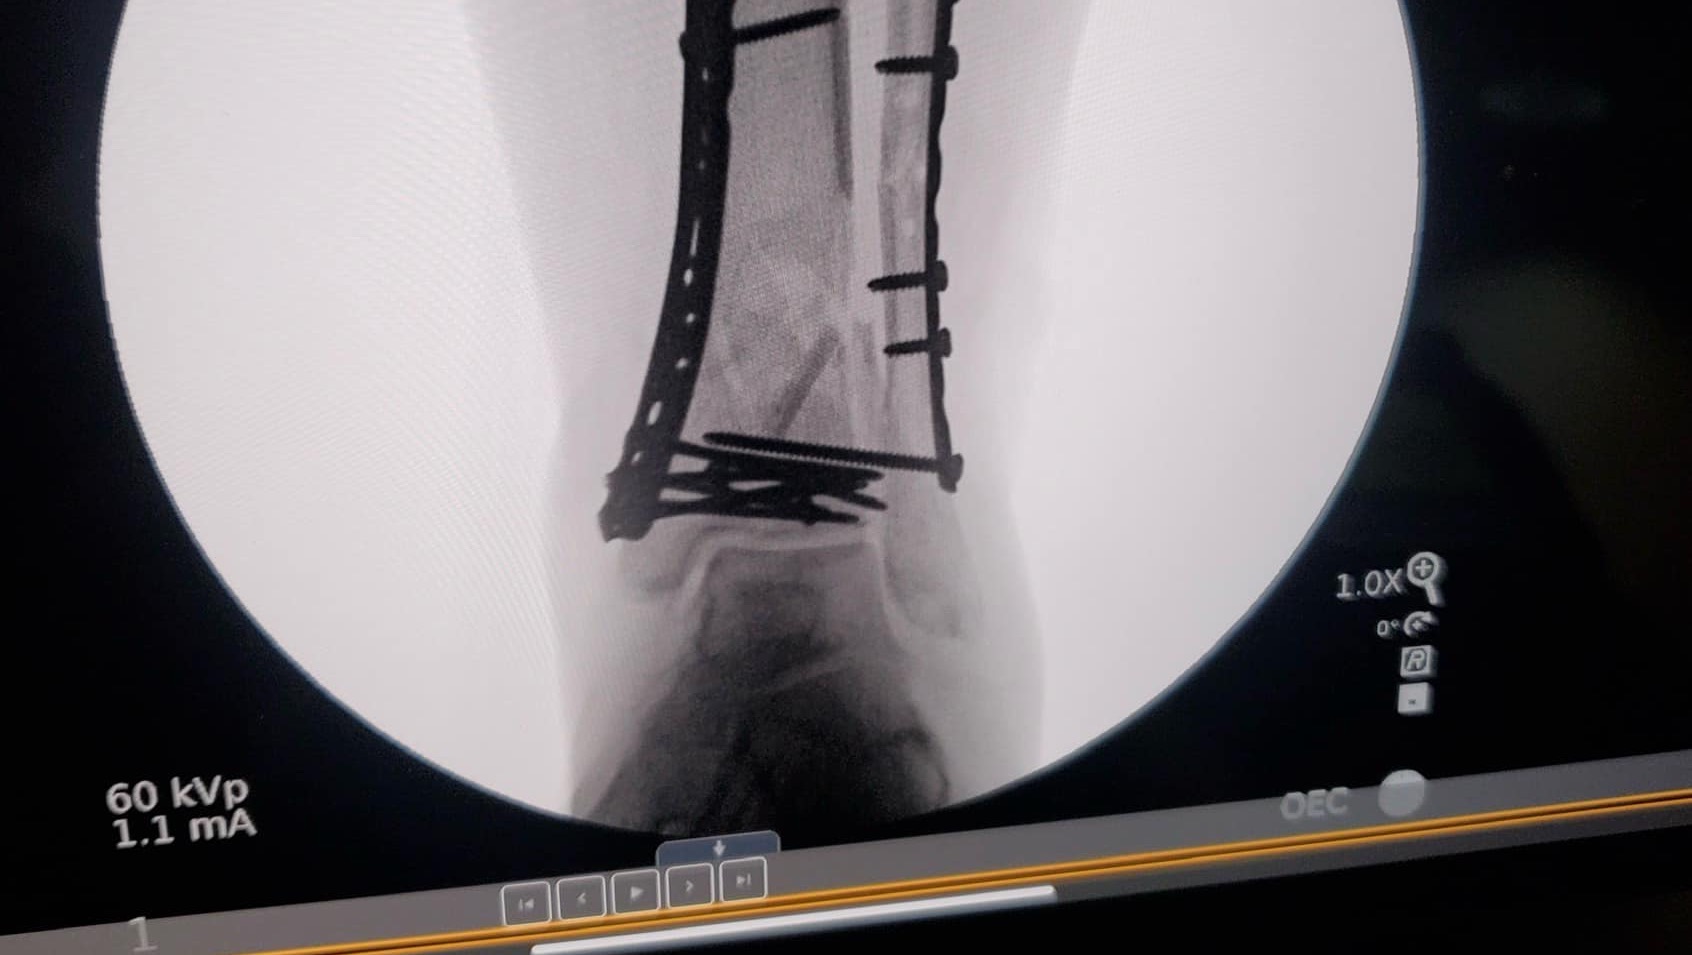

On February 12th, my close friend lost her job. Six days later, she broke her leg in a very, very bad way. She fractured both her tibia and fibula, injured her ankle joint, and the bone broke through the skin. It was a very serious, life-threatening situation. She has been in a trauma hospital to address the severity and set the leg to begin healing, moved to an assisted living facility while waiting for swelling to go down in order to have surgery to add hardware, back to the hospital for said surgery, and now to a rehab center.